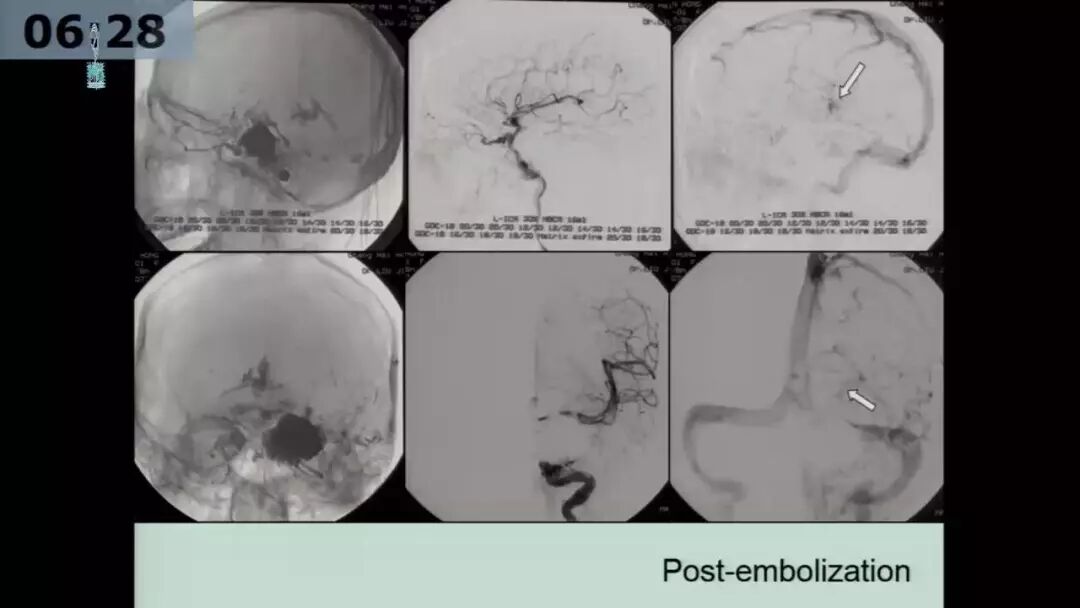

许奕教授:海绵窦区脑膜动静脉瘘的介入治疗